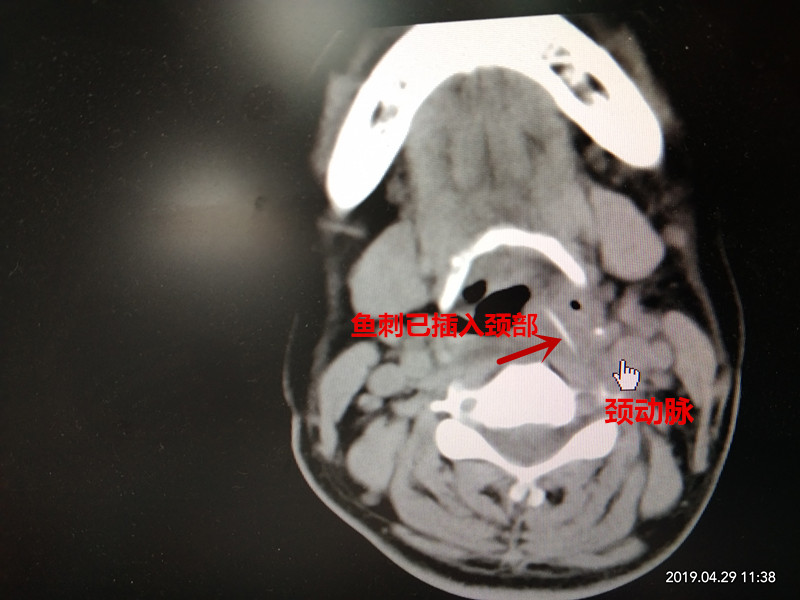

“喉镜检查我们发现患者左侧下咽及黎状窝已经肿胀糜烂,但看不到鱼刺。”接诊医师宋忠云说,凭借经验他考虑鱼刺很有可能已经刺入咽旁组织内,随后结合CT检查发现颈部有一根约3公分鱼刺,已经快要到达颈椎,而且临近颈动脉,如果再得不到正确的治疗可能会伤及颈部的血管和神经等,甚至会危及生命。